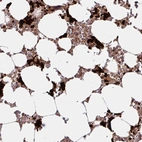

Immunohistochemistry analysis in human bone marrow and cerebral cortex tissues using Anti-HMBS antibody. Corresponding HMBS RNA-seq data are presented for the same tissues.